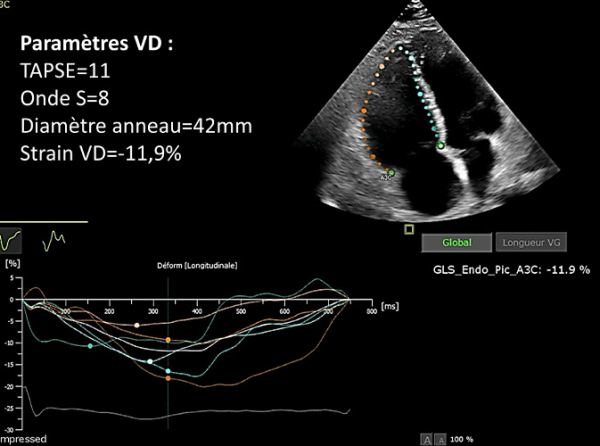

- FEVG 60%, dilatation VD sévère, PAPs=65mmHg

- Paramètres VD : TAPSE=11 - Onde S=8 - Diamètre anneau=42mm - Strain VD=-11,9%

Figure 2 : ETT - Strain VD